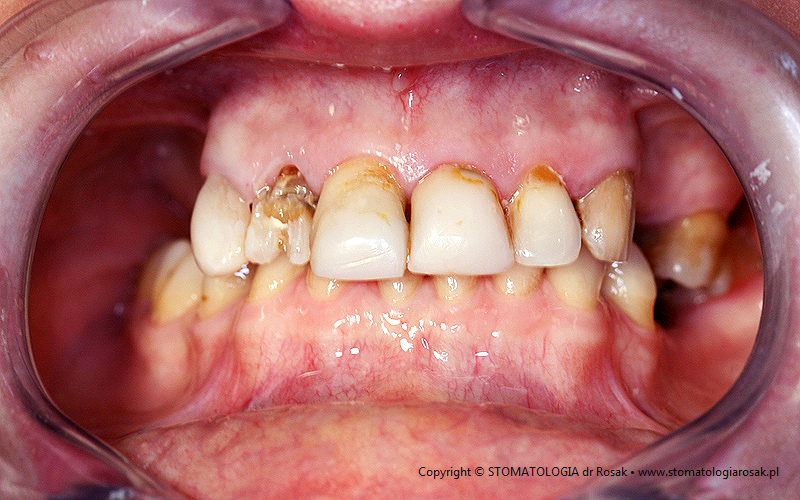

9. Pacjent lat 57- zgłosił się celem usunięcia zniszczonych zębów i wykonania protez ruchomych całkowitych.

NIE USUNĘLIŚMY - ANI JEDNEGO ZĘBA!!!

| 9a. Przed leczeniem |

9b. Gotowe korony i mosty porcelanowe na górze

(trójkę górną prawą pacjent zażyczył sobie nie korygować)

oraz w żuchwie tzw. czapeczki pokrywające oraz zatrzaski kulowe dla lepszego utrzymania protezy ruchomej dolnej |